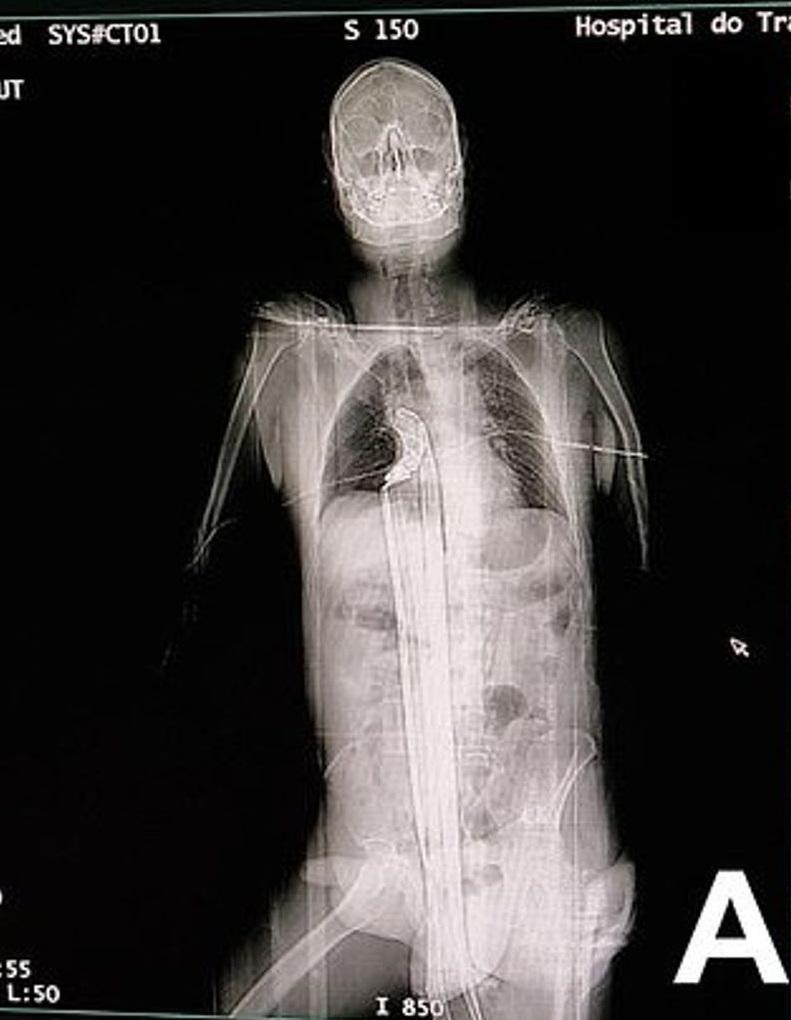

掃描圖像顯示,長鋼條從男子下體插進體內,直到肺部下方。(互聯網)

醫生指,該名男子被長約91厘米的鋼條,從下體插入並貫穿上半身,插到肺部與橫隔膜附近位置,肝臟被穿刺,所幸避過心臟。男子被送院急救,醫生初步檢查發現,其心率、血壓和血氧狀況,出奇地都正常。